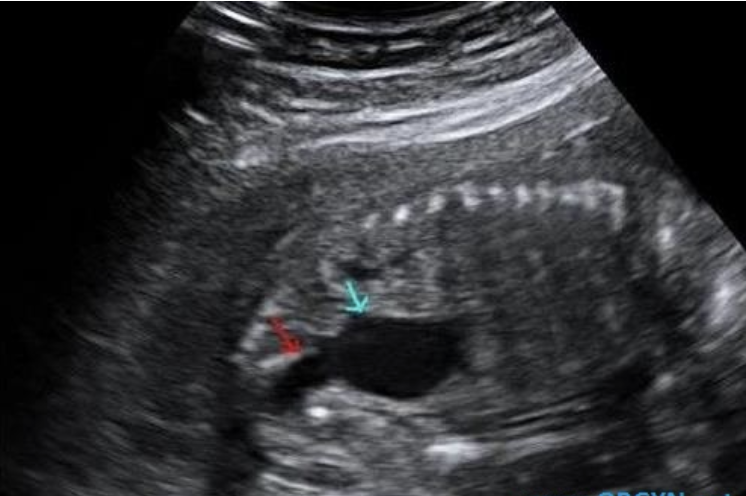

what congenital anomaly is shown

a) renal agenesis

b) duodenal atresia

c) anal atresia

d) posterior urethral valves